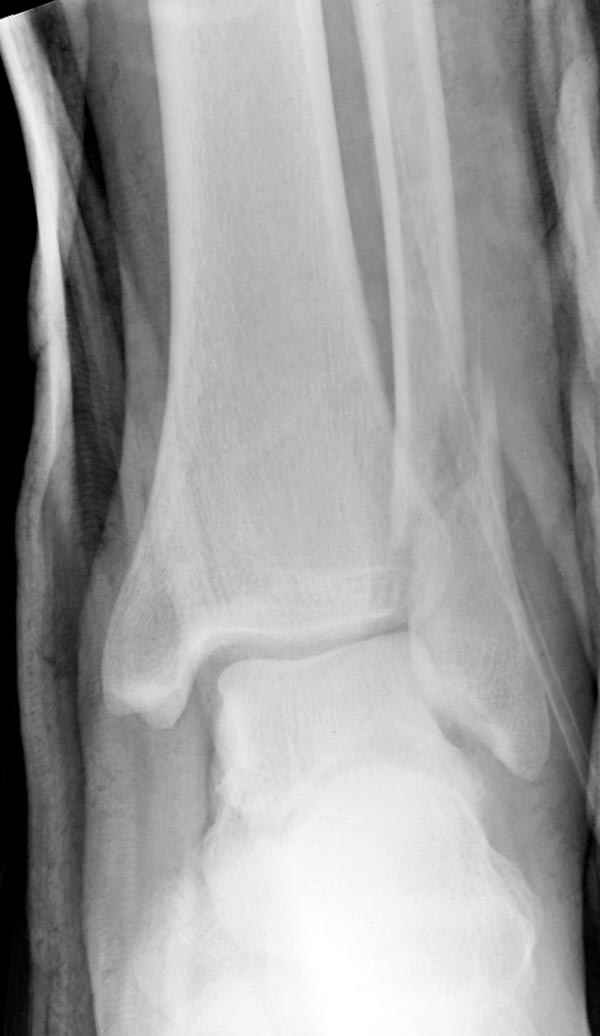

Тему неоднократно разбирали (см. архив), как всегда, недостаточны ренгенологические исследования - кроме прямого и боковых снимков, еще нужна косая ренгенограмма для определения ankle mortise, без мортиз снимка трудно определить высоту и ротацию малоберцовой. (снимки)

Ренгенология даст ответ как классифицировать перелом, на сегодня применяется классификация “Lauge Hansen fracture classification SER supination-external rotation или supination-eversion classification Danis

Weber А, В, С.”

Показания для фиксации: укорочения и ротация малоберцовой, особенно обращают внимание на любой подвывих таранной кости: неустраненый подвывих впоследствии приводит к раннему артрозу. Задний край фиксирует тогда, когда перелом составляет около 25% суставной поверхности голеностопного сочленения и смещение более 2мм.

По снимку ваш случай относится к Weber В, фиксацию производят восстановлением длины малоберцовой кости, под ренгеном (ЭП)контролем, для этого я предпочел бы латеральный доступ, остеотомия по линии перелома, удлинение малоберцовой засчет скоса линии остеотомии, компрессия “lag technique”по линии остеотомии и фиксацию провести латеральной пластиной. Отдельный задний доступ, остеотомия по линии перелома, репозиция и фиксация заднего края вашим предпочтительным методом: 3.5мм шурупом с шайбой или пластиной Antiglide Butress